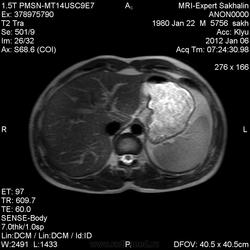

МРТ брюшной полости.Добавочная селезенка и расширенная портальная вена.

Уважаемые коллеги, первый "блин" в этом году.Молодой человек с жалобами на боли опоясывающего характера в гипогастрии.Сообщает, что подозревали синдром Жильбера.Пришел самостоятельно, без направления.Меня заинтересовала расширенная портальная вена с наличием тромботических масс(?) и селезенка.Что скажете?Малоопытная я в этих дела.

Пожалуй, насчет тромботических масс погорячилась.Наверное, это артефакты от тока крови?

Тромбоза на мой взгляд нет, расширение портальной вены если и есть - небольшое.

Мне добавочные селезёнки чаще попадаются у верхнего полюса или в воротах, размерами поменьше. Панкреатита вроде не видно. Может, герпес (я про опоясывающие боли)?

Спасибо за комментарии!Написала только добавочную селезенку и перегиб шейки желчного пузыря.